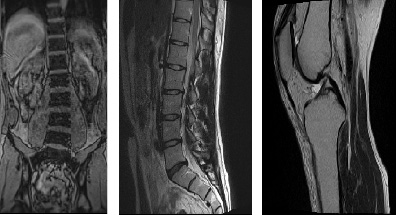

MRI 装置の撮影画像

膝や腰椎の画像